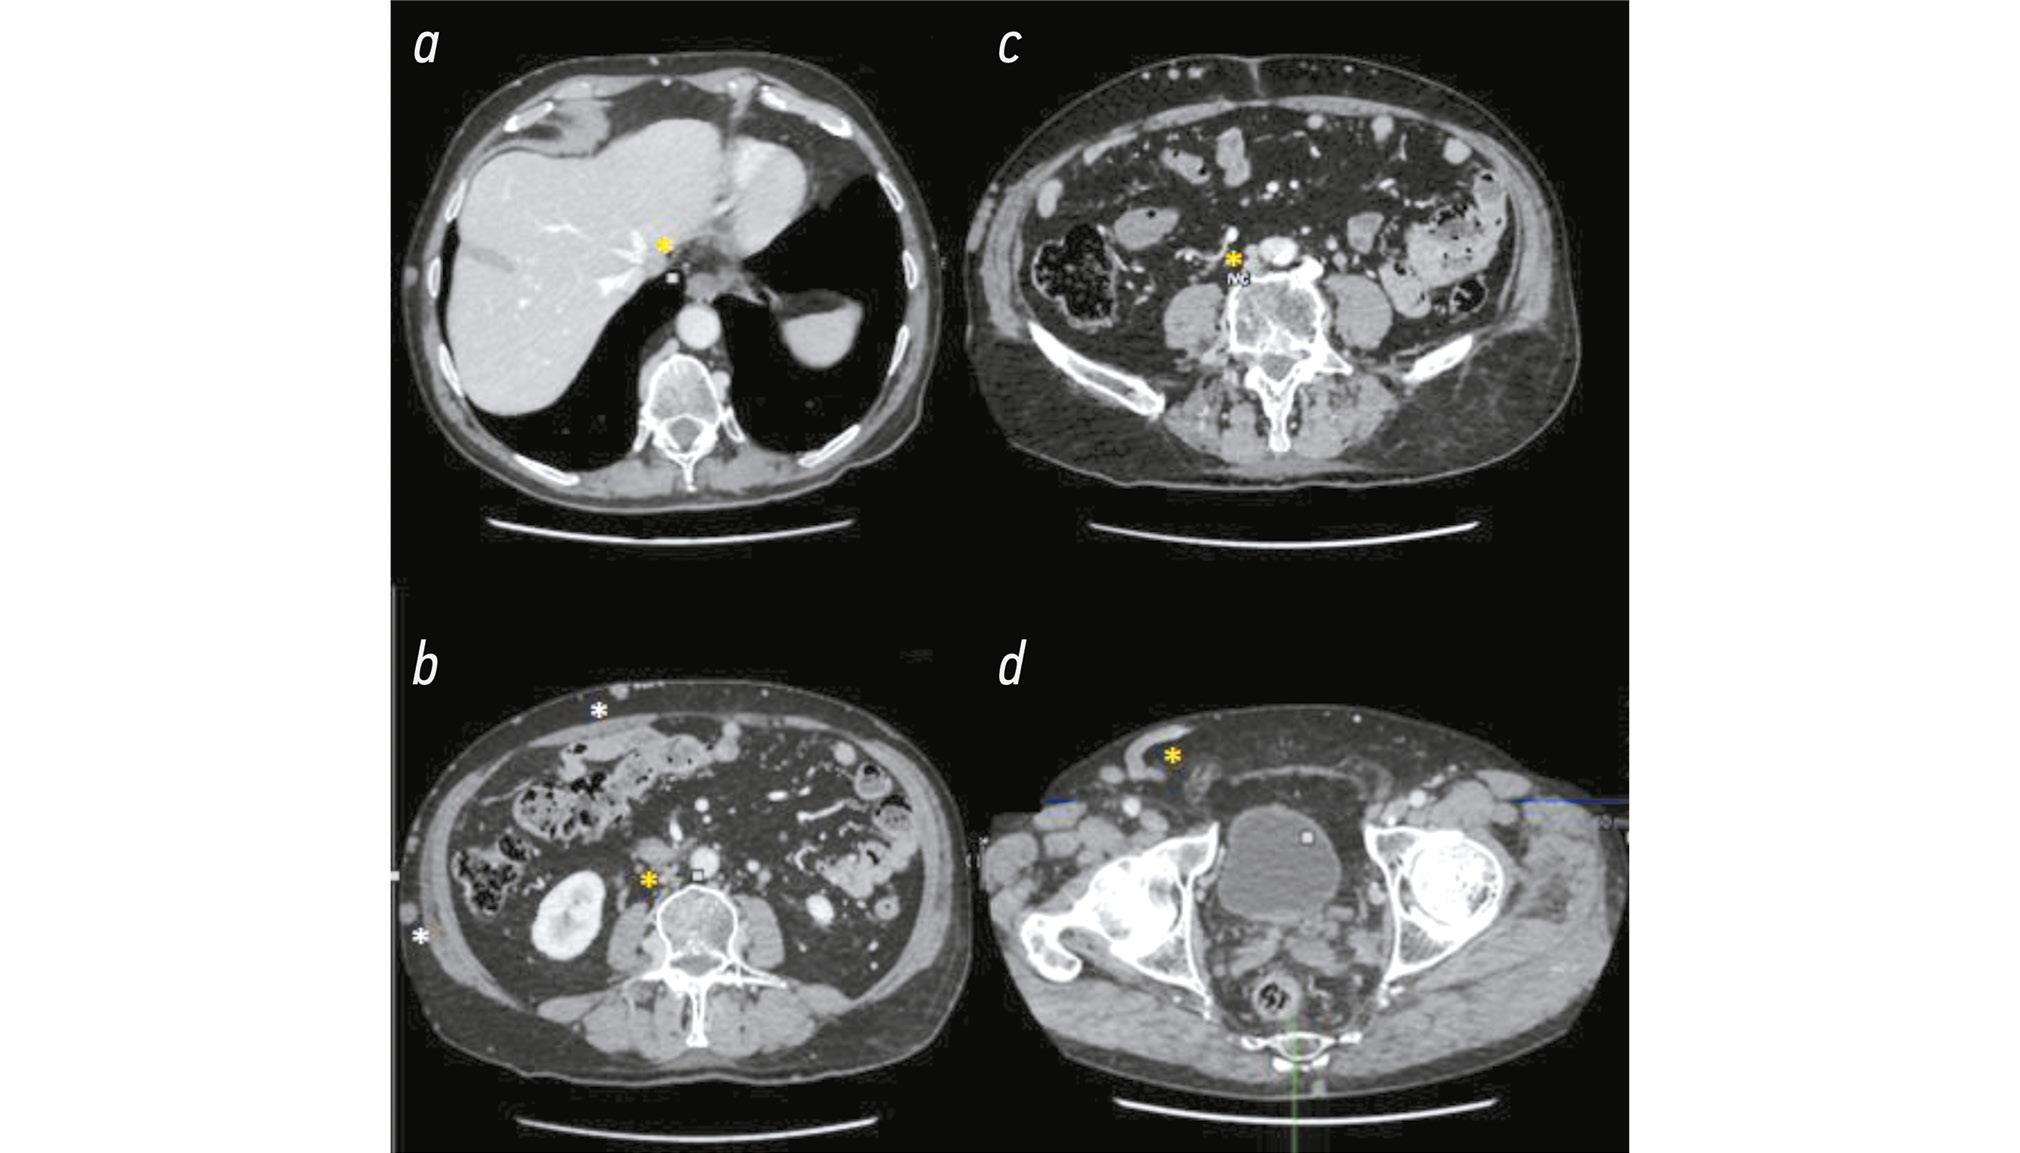

At first glance, the most evident imaging finding of the vascular anomaly was the presence of multiple collateral venous circles on the anterior wall of the abdomen, particularly on the right side, and the IVC under the kidneys was hypoplastic (Fig. 2).

Fig. 2. Computed tomography images of the coronal (up) and sagittal (down) sections in the portal phase of the chest and abdomen: a) Right abdominal wall: consistent venous collateral circles are visible (white asterisk). b) The same image with a rising MIP value indicates venous collateral rings, particularly on the patient’s right side. c) and d) Hypertrophic venous collateral circles in the sagittal section at different levels.